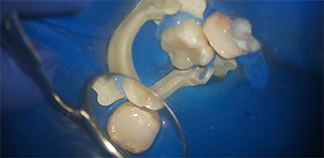

До лечения

Жалобы на стирание и отсутствие зубов.

Пациенту 63 года.

Как лечили

Удалены разрушенные зубы. Восстановлены отсутствующие зубы коронками. Изготовлены съемные протезы.

Лечение проведено в течение шести месяцев.